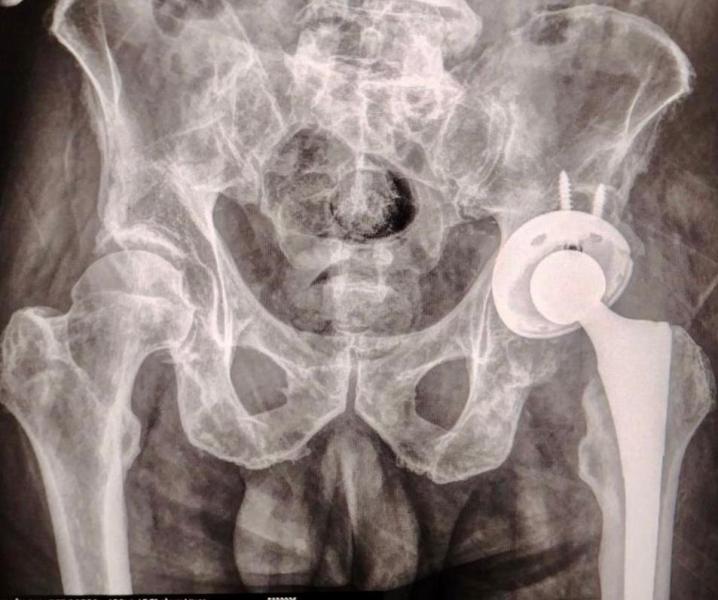

ISSSTEP realiza con éxito primera prótesis de cadera sin costo

CIUDAD DE PUEBLA, Pue.-Julio 22 del 2025.– El Gobierno del Estado de Puebla a través del Instituto de Seguridad y Servicios Sociales de los Trabajadores al Servicio de los Poderes del Estado de Puebla (ISSSTEP), realizó con éxito y bienestar la colocación de la primera prótesis de cadera sin costo para el paciente, un nuevo hito en el fortalecimiento de sus servicios médicos de alta especialidad.

La intervención quirúrgica fue realizada por un equipo multidisciplinario altamente capacitado, bajo estrictos protocolos de seguridad y criterios clínicos de selección. Este procedimiento representa un paso significativo en la atención integral de padecimientos osteoarticulares, particularmente en pacientes con desgaste articular severo que afecta su calidad de vida y movilidad.